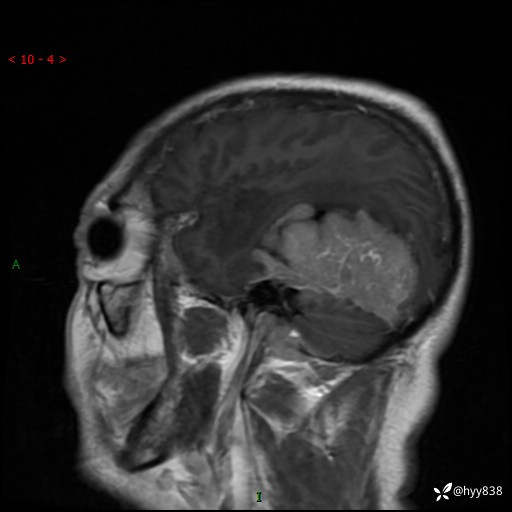

患者性别:男

患者年龄:56岁

简要病史:外院CT提示脑膜瘤,为进一步诊治来我院

辅助检查:MRI

临床诊断:颅脑占位

颅脑MRI平扫+增强